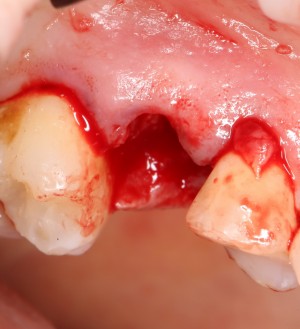

Ну и, зуб проще удалить, если ты видишь, что от него осталось. Что мы и делаем:

Вместе с зубом удаляется прикорневая гранулема. После того, как из лунки удалены все патологически измененные ткани, можно подумать о том, как сохранить объемы альвеолярного гребня в этом участке для будущей имплантации.